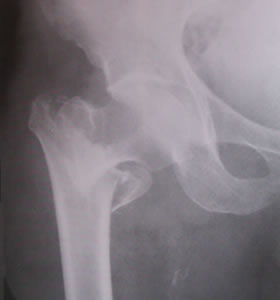

As fraturas podem ocorrer em todos os ossos, mais são mais comuns no quadril, coluna e punho. Destas, a mais grave é a que ocorre no quadril, pois quase sempre é de tratamento cirúrgico e se associa com grande numero de mortes que pode ocorrer no momento da cirurgia ou no período pós operatório.